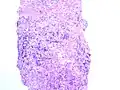

Die Einteilung umfasst ursprünglich fünf Grade, welche sowohl die Form, als auch die Anordnung der Drüsen beschreibt. Die Grade 1 und 2 sollen jedoch nicht mehr vergeben werden.[2] Grad 3 beschreibt kleine ungleichmäßige Drüsen, Grad 5 beschreibt die am schlechtesten differenzierten Tumoren, deren Wachstumsmuster fast jede Ähnlichkeit mit normalem Prostatagewebe verloren haben, Grad 4 liegt dazwischen.[3]

Gleason Grad 3 und 4 -

Gleason Grad 5